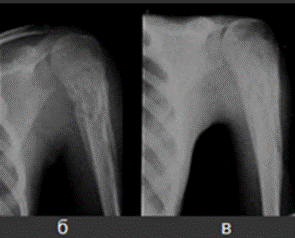

При своєчасному і правильному лікуванні запальний процес може бути перерваний і швидко повністю ліквідовано (рис.3).

Рис.3. Динаміка раневого остеомієліту (поранення голкою) у дитини 9 років під впливом введення антибіотиків в уражену кістку (одна ін'єкція в день протягом 4 днів). При першому обстеженні - припухлість і почервоніння шкіри в нижній третині передпліччя, пальпація різко болюча, температура тіла 37,8 ͦ. а - рентгенограма через 10 днів після поранення і через 3 дні від початку лікування: променева кістка на межі середньої та нижньої третини дещо потовщена, щільність її збільшена за рахунок періостальних нашарувань; б - через 1 місяць після першої рентгенограми: клінічно - повне затихання процесу, болю немає, температура тіла нормальна, аналіз крові без патології, кістка стала значно товщі за рахунок періостальних нашарувань; в - ще через 1 місяць: клінічно - повне одужання, пальпація і все навантаження безболісні, кістка залишається потовщеною за рахунок періостальних нашарувань, які зменшилися в обсязі, стали рівними, чіткими; г - ще через 4 місяці - повна нормалізація форми і структури кістки.